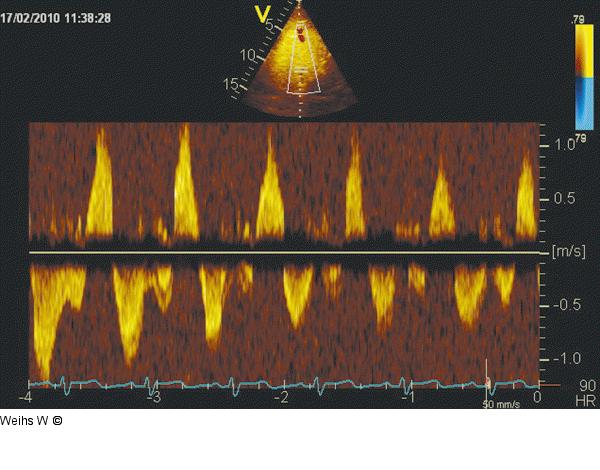

Abbildung 8: Lebervenenfluss Der Lebervenenfluss (im subkostalen Schnitt) zeigt bei hochgradiger Trikuspidalinsuffizienz einen stark verminderten systolischen Vorwärtsfluss bei gleichzeitig ausgeprägtem Rückfluss, der während der Inspiration noch verstärkt wird. |

Der Lebervenenfluss (im subkostalen Schnitt) zeigt bei hochgradiger Trikuspidalinsuffizienz einen stark verminderten systolischen Vorwärtsfluss bei gleichzeitig ausgeprägtem Rückfluss, der während der Inspiration noch verstärkt wird. |